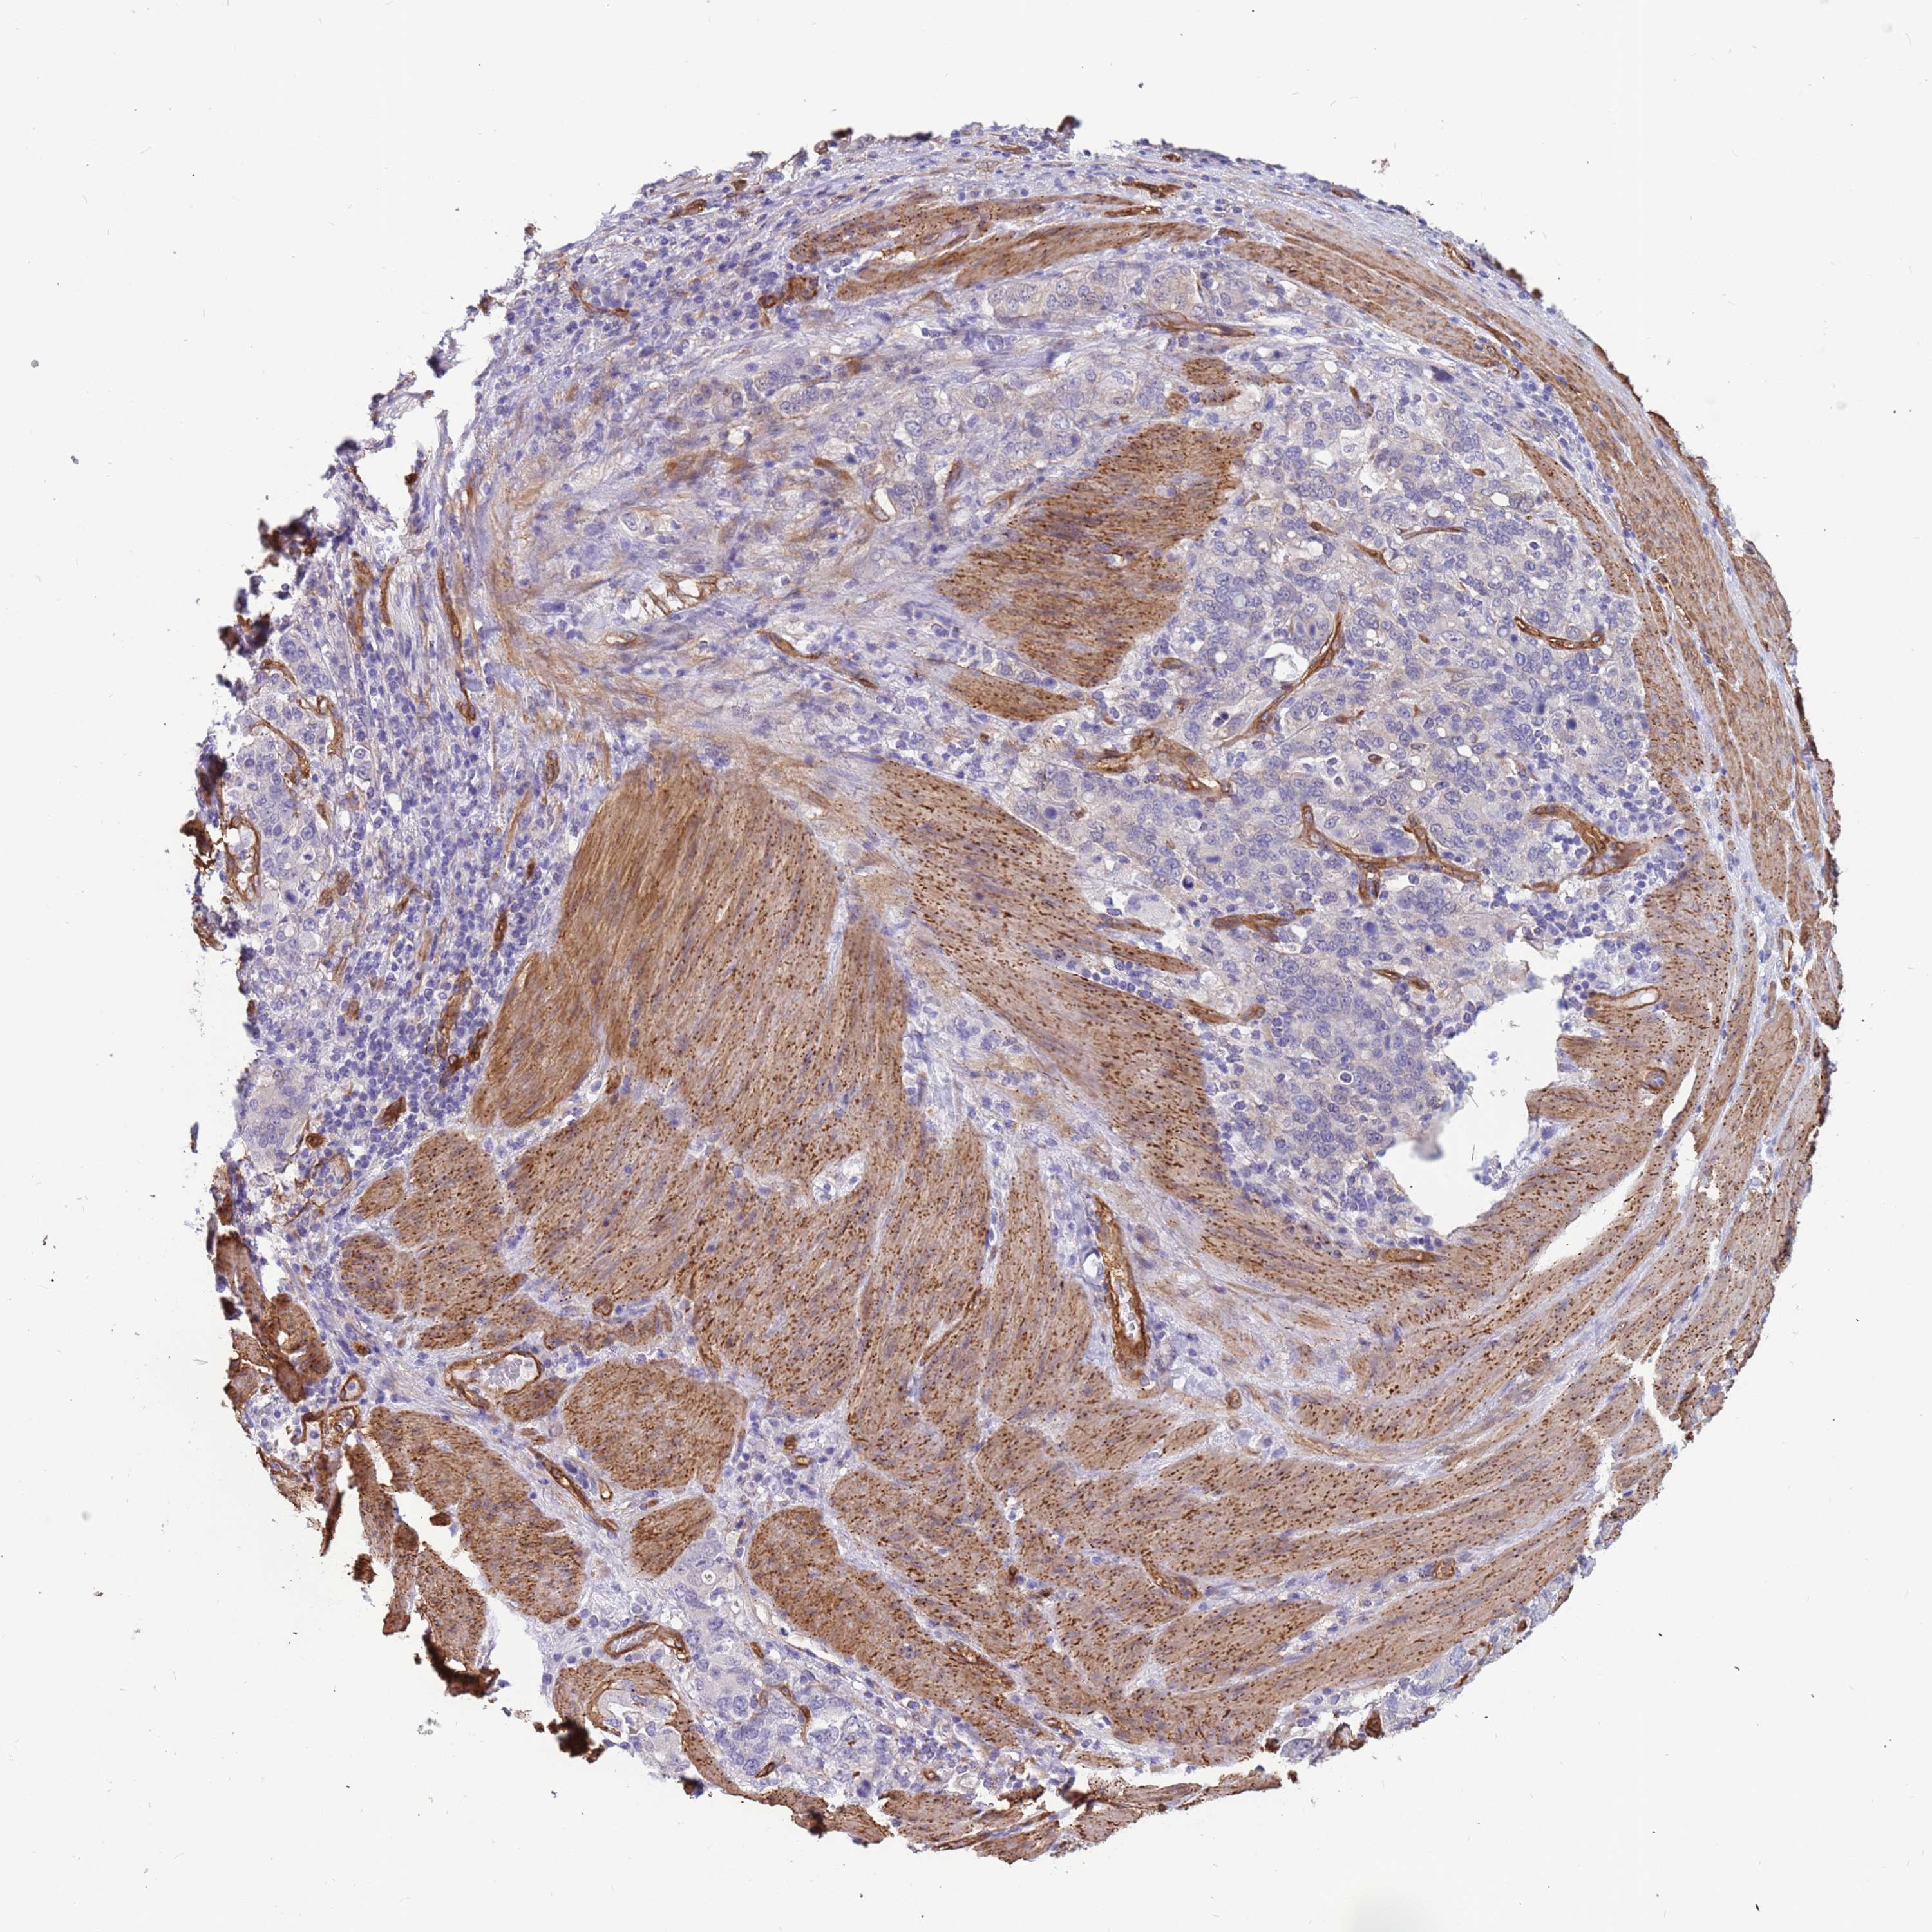

STOMACH CANCER - Protein expressioni

A mouse-over function shows sample information and annotation data. Click on an image to view it in a full screen mode. Samples can be filtered based on level of antibody staining by selecting one or several of the following categories: high, medium, low and not detected. The assay and annotation is described here.

Note that samples used for immunohistochemistry by the Human Protein Atlas do not correspond to samples in the TCGA dataset.

Antibody stainingi

Antibody staining in the annotated cell types in the current human tissue is reported as not detected, low, medium, or high, based on conventional immunohistochemistry profiling in selected tissues. This score is based on the combination of the staining intensity and fraction of stained cells.

Each image is clickable and will lead to virtual microscopy that enables deeper exploration of all samples and also displays staining intensity scores, fraction scores and subcellular localization as well as patient and tissue information for each sample.

Antibody HPA047394

Antibody HPA049890

Antibody HPA049986

Staining

Adenocarcinoma, NOS